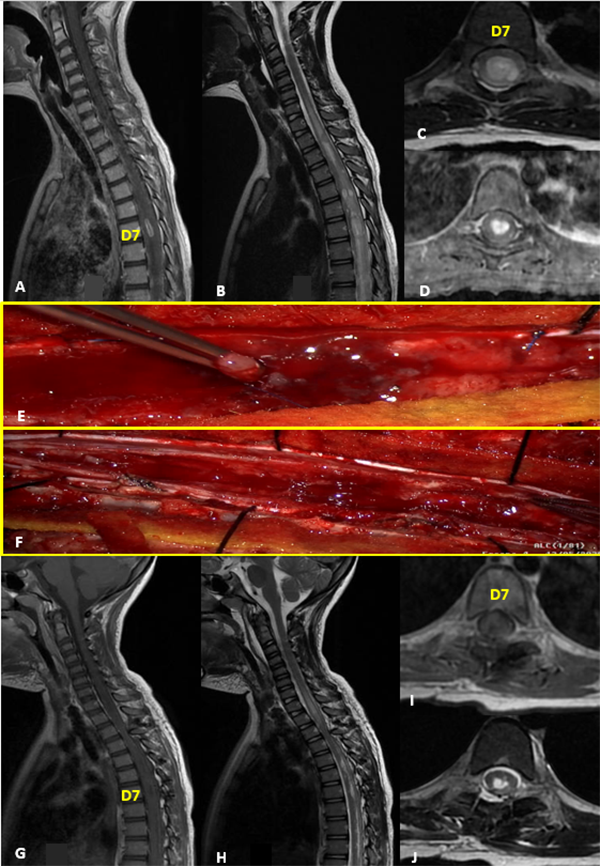

IV: Glioma Difuso de Bajo Grado

Paciente sexo femenino que a los 9 meses se le realizó exéresis total de tumor intramedular cervico-dorsal (C1-D4) en otra institución, cuyo diagnóstico anatomopatológico informó ependimoma de alto grado, por lo que completó tratamiento adyuvante con quimioterapia (6 ciclos de cisplatino, etopósido, vincristina y ciclofosfamida según protocolo HeadStart II), con posterior trasplante autólogo de médula ósea. Inicialmente debutó con falta de adquisición en las pautas motoras asociado a paresia de miembros superiores. En el postoperatorio evolucionó con cuadriparesia e hidrocefalia requiriendo colocación de shunt ventrículo peritoneal. A los 2 años de vida en los controles de RM se evidencia marcado refuerzo postcontraste y engrosamiento de las raíces de la cauda equina, destacándose a la altura de L2, una imagen nodular con intensa captación de contraste, que medía 6 x 5 x 6 mm aproximadamente. Se realizó la resección completa de la lesión. La anatomía patológica reveló glioma difuso de bajo grado (Grado II de la OMS) (Figura 4).

Figura 4: Glioma Difuso de Bajo Grado. A-D: RM prequirúrgica T1 con contraste y T2 cortes axiales y sagitales. E-G: RM postquirúrgica alejada que evidencia resección completa de tumor cervical con lesión metastásica nodular a nivel de L2 (flecha roja). H: Imagen intraoperatoria de la lesión.